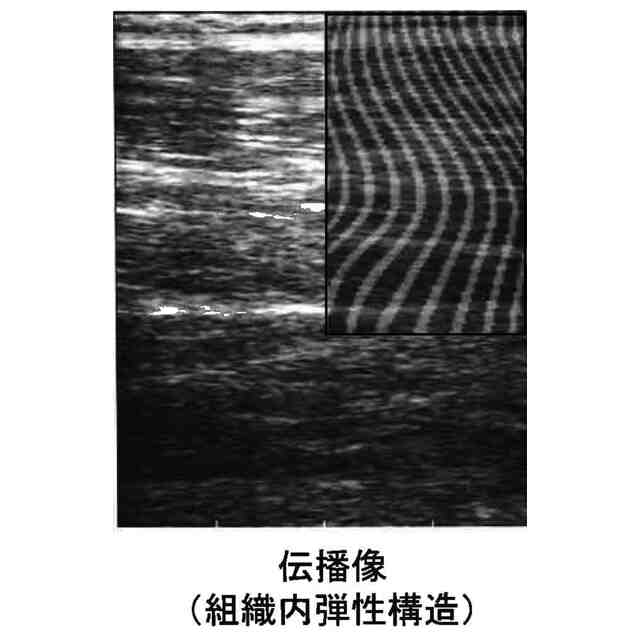

特に、生体組織への加振器を用いて、生体物の関節構造体を動かすための筋肉、筋、腱といった運動機能に関わる所定の生体組織(以下本発明において「運動機能組織」という)を所定の周波数で振動させて機械振動波を発生させ、この振動波を発生させた状態のまま、生体表面に押し当てた超音波プローブによって運動機能組織内を伝わる機械的な振動波(横波)の伝播速度をせん断波伝播速度推定によって算出し、また算出結果を画像化し、これらによって当該運動機能組織の生体硬さを測定結果として出力し、もって運動機能組織の運動機能(筋肉、動きを起こす筋、神経伝達機能)の状態及び働きを評価する状態表示システム、並びに評価方法に関する。

【0006】

超音波を用いて生体物(人体又は動物)の生体組織を映像化する超音波映像方法として、従来、WO2015/151972(特許文献1参照)が開示される。同開示においては、穿刺針を測定部近くの体表に押し当てて穿刺部の生体細胞を振動させた状態で、超音波エコー装置によって生体組織内を伝わる機械的な振動波(横波)の伝播速度を画像化している。